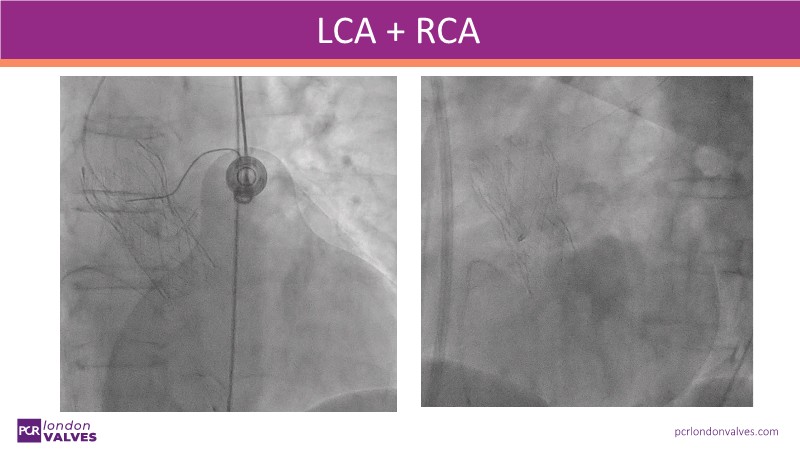

- To learn how to perform TAVI resulting in commissural alignment and easier coronary access